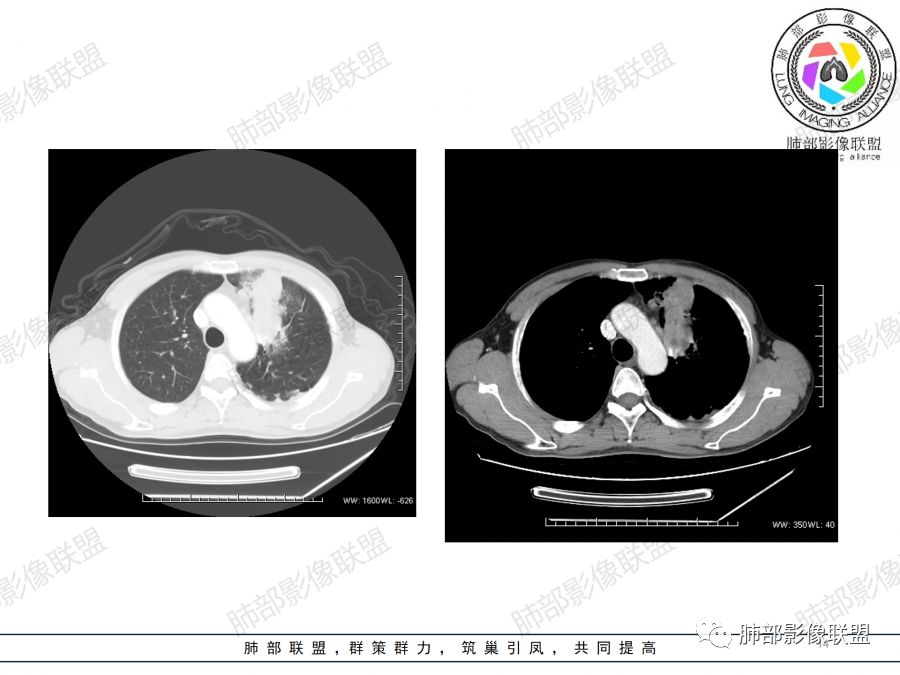

胸CT:左上叶前段团块影,边缘部分清晰,近纵隔侧膨隆明显,分叶,肺侧见平直征,U形凹陷,病灶周围可见磨玻璃影,气肿带,纵隔多发淋巴结肿大,叶间裂多发小结节。增强病灶内密度不均,散在斑片状低密度区,血管造影征。考虑:恶性,鳞?腺?大细胞?鉴别:炎症。似有左侧胸廓内A供血病灶,SFT?

男,47岁,咳嗽咳痰一月余入院肺气肿背景。左上肺纵隔旁非均质肿块,分叶、膨隆,部分边缘光滑,肺门可见冰冻征,增强不均匀强化,见沼泽地样坏死,邻近肺组织见斑片状炎症,考虑恶性肿瘤,首先考虑小细胞癌,鉴别鳞癌。

中年男性,左肺上叶肿块、片状状影,形态不规则,边缘见分叶及磨玻璃影,其内可见斑片状低密度区及血管穿行。增强扫描呈轻度强化,侵犯纵隔及部分胸膜,纵隔见多发淋巴结肿大,定位:肺内,左上肺部分有不张;定性:偏恶性,侵犯支气管(病灶内见条状低密度影)但血管无明显受累,考虑粘膜相关性淋巴瘤(粘膜下起源)可能,结核待排;腺癌、鳞癌(血管无受侵不首先考虑),小细胞(无典型表现、虽然血管保留可见于小细胞);

男,47岁,咳嗽咳痰一月。病灶位于左内乳动脉内缘,定位肺内,呈团片状异常密度影,整体沿支气管气管束走形分布,由肺门达胸膜下,于近肺门侧病灶形态相对较小,病灶远端相对较大,病灶整体密度偏均匀,强化偏明显,病灶内见多发支气管扩张并粘液栓形成,且扩张支气管粗细不均,直达病灶以远,病灶内血管走形正常、粗细均匀,病灶周围见边缘模糊磨玻璃及少许腺泡结节。左肺门及纵隔略大淋巴结,左侧胸膜局限性增厚。诊断:左肺上叶前段异常密度影,炎性肉芽肿性病变可能,结核不能除外,建议穿刺活检除外恶性肿瘤。

1.左肺上叶尖后段体积变化不大,病灶长轴沿支气管血管束向肺门侧生长,

2.病灶外围大,内带小,外朝内蔓延

3.病灶边缘以收缩为主,局部稍膨隆,

4.病灶整体轻中度强化,强化较均匀,局部见多个管状低密度影,边界清,考虑支气管粘液栓;病灶局部可小灶样的低密度区,未见强化,考虑坏死灶,坏死灶周围见明显强化的壁,壁清楚、光整,未见中断,倾向炎性肉芽肿的坏死;

5.病灶内血管部分走形自然,部分走形僵直、粗细不均,提示病灶有部分破坏力,但是不强;

6.病灶与纵隔胸膜呈“糊墙”样改变,倾向炎性病灶;

6.纵隔淋巴结肿大,密度均匀,强化均匀;

本病例未行冠矢状位重建,未提供连续薄层图像,病灶与支气管情况呈现不满意。

2.双上肺多发病灶,左肺上叶病灶沿血管支气管束分布,由外朝内,以平直收缩为主,周围有斑片渗出,胸膜糊墙,支持炎性病灶或是伴有肿瘤灶可能性。

两上肺发病,多支持结核等感染,但结核基础上伴发肺癌并不鲜见!

3.病灶内多支支气管粘液栓,炎性及恶性均可,但是炎性多于恶性;强化杂乱不均,病灶内小灶坏死比规则,支持炎性肉芽肿病变。

鳞癌病灶如较大,强化常不够显著且多见相对大范围湖泊样坏死。

5.  本例的焦点主要集中在结核与周围型肺鳞癌的鉴别诊断上!

病灶与大气道的关系未能满意呈现,但如此大范围病灶紧贴胸膜却未见胸壁纵隔组织结构侵犯破坏是不大符合肺鳞癌的生物学行为的。